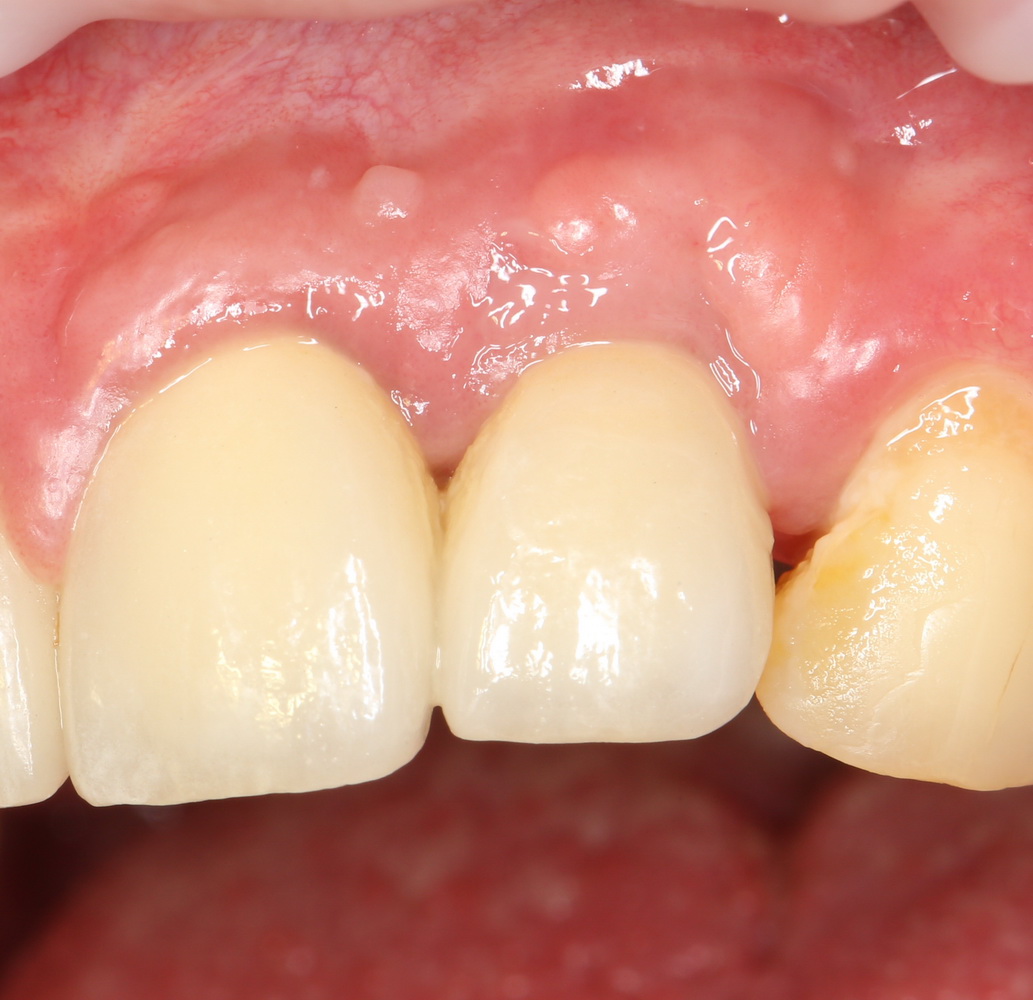

Около трёх лет назад к нам в клинику обратилась пациентка Мария, на момент обращения ей было 45 лет. Её беспокоила ситуация с передними резцами:

В ходе беседы она рассказала, что лечит эти зубы всю сознательную жизнь — их депульпировали («удалили нерв») из-за последствий травмы еще в школьном возрасте, и после этого каждые несколько лет (а то и чаще) ей приходилось перелечивать каналы, менять коронки, вкладки и т. д.

В результате, зубы приобрели очень уж нездоровый вид (см. фото выше). Вдобавок, всё усугубилось существенным снижением качества жизни — коронки и вкладки из зубов постоянно выпадают, десна вокруг них кровоточит при чистке…. Кроме того, Марию не покидает ощущение того, что эти зубы могут просто вывалиться в самый неподходящий момент. Именно это заставило её обратиться в нашу клинику.

Визуальный осмотр:

Подвижность зубов (или коронок) II-III степени косвенно свидетельствует о разрушении периодонтальных связок и стенок лунок зубов. Подвижность является следствием хронического воспаления, когда окружающие зуб ткани остаются без питания и деградируют — и в совокупности это может существенно осложнить сохранение эстетических параметров окружающих имплантат тканей. Степень риска — высокая.

Слизистая оболочка в области центральных резцов отёчна, при прикосновении кровоточит — прямое следствие хронического воспаления. Пока слизистая оболочка воспалена, она не способна к регенерации. Это значит, что операционные раны на такой слизистой вряд ли будут нормально заживать. Степень риска — высокая.

Рецессия десны из-за хронического воспаления — признак запущенного длительного существующего воспалительного процесса, в результате которого разрушается, в том числе, костная ткань. В таких условиях её регенеративная способность, не говоря уже свойствах десны, существенно снижается. Скорее всего, на КЛКТ мы увидим утрату вестибулярной стенки лунки (что объясняет подвижность). Степень риска — высокая.